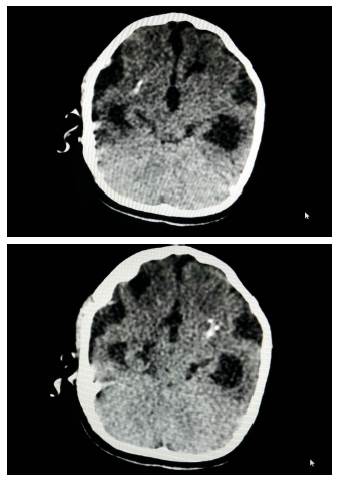

(5/04/2017). Examen físico: muestra talla < -3 SD, peso < -3 SD y perímetro cefálico < -3 SD. Cráneo con fontanela cerrada. Examen neurológico: se encuentra en el campo motor hipertonía con hiperreflexia, DPM correspondiente para un mes de edad. El TAC cerebral simple (Figura 2) reporta dilatación simétrica de los ventrículos laterales, imágenes hiperdensas focales hacia los lóbulos parietales, normalidad de las cisternas perime-sencefálicas, tallo y fosa posterior. El EEG enseña un trazado en sueño NREM uno y dos normal. Concepto clínico es de retraso en el desarrollo psicomotor (RDPM) y microcefalia por Zika.